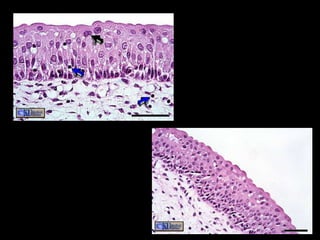

Pseudostratified Epithelium

• Structure

– Irregularly shaped cells with nuclei at different

levels – appear stratified, but aren’t.

– All cells reach basement membrane

• Function

– Absorption and Secretion

– Goblet cells produce mucus

– Cilia (larger than microvilli) sweep mucus

• Location

– Respiratory Linings & Reproductive tract

Pseudostratified Epithelium • Structure –Irregularly shaped cells with nuclei at different levels – appear stratified, but aren’t. – All cells reach basement membrane • Function – Absorption and Secretion – Goblet cells produce mucus – Cilia (larger than microvilli) sweep mucus • Location – Respiratory Linings & Reproductive tract